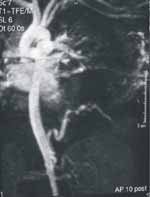

La angiorresonancia es reportada como secuestro alimentado por una arteria sistémica de alto flujo originada en la aorta abdominal; el drenaje venoso era infradiafragmático. En vista de los hallazgos se llevó a toracotomía posterolateral izquierda, el día 18 de vida, sin presentar ningún deterioro clínico durante este tiempo (ver Figura 4).

Figura 4. Angiorresonancia. Irrigación del secuestro pulmonar originada en la aorta abdominal.